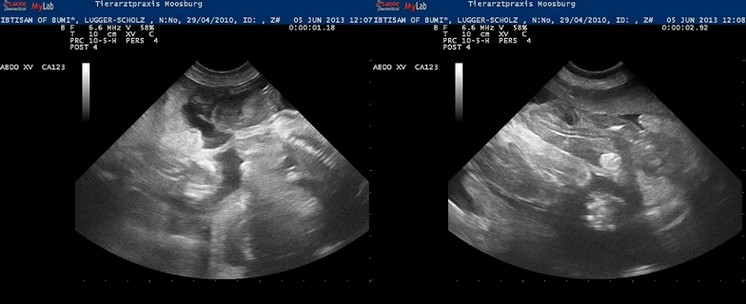

05.06.2013

Es gibt neue Ultraschallbilder… Wir waren heute wieder beim Tierarzt… Herr Dr. Volker Moser machte ein paar tolle Aufnahmen. Man kann mittlerweile die einzelnen Welpen gut erkennen, sieht die kleinen Wirbelsäulen und kann die kleinen Herzen beim Schlagen bewundern… Es ist so aufregend…!

Ein Video davon gibt es hier.